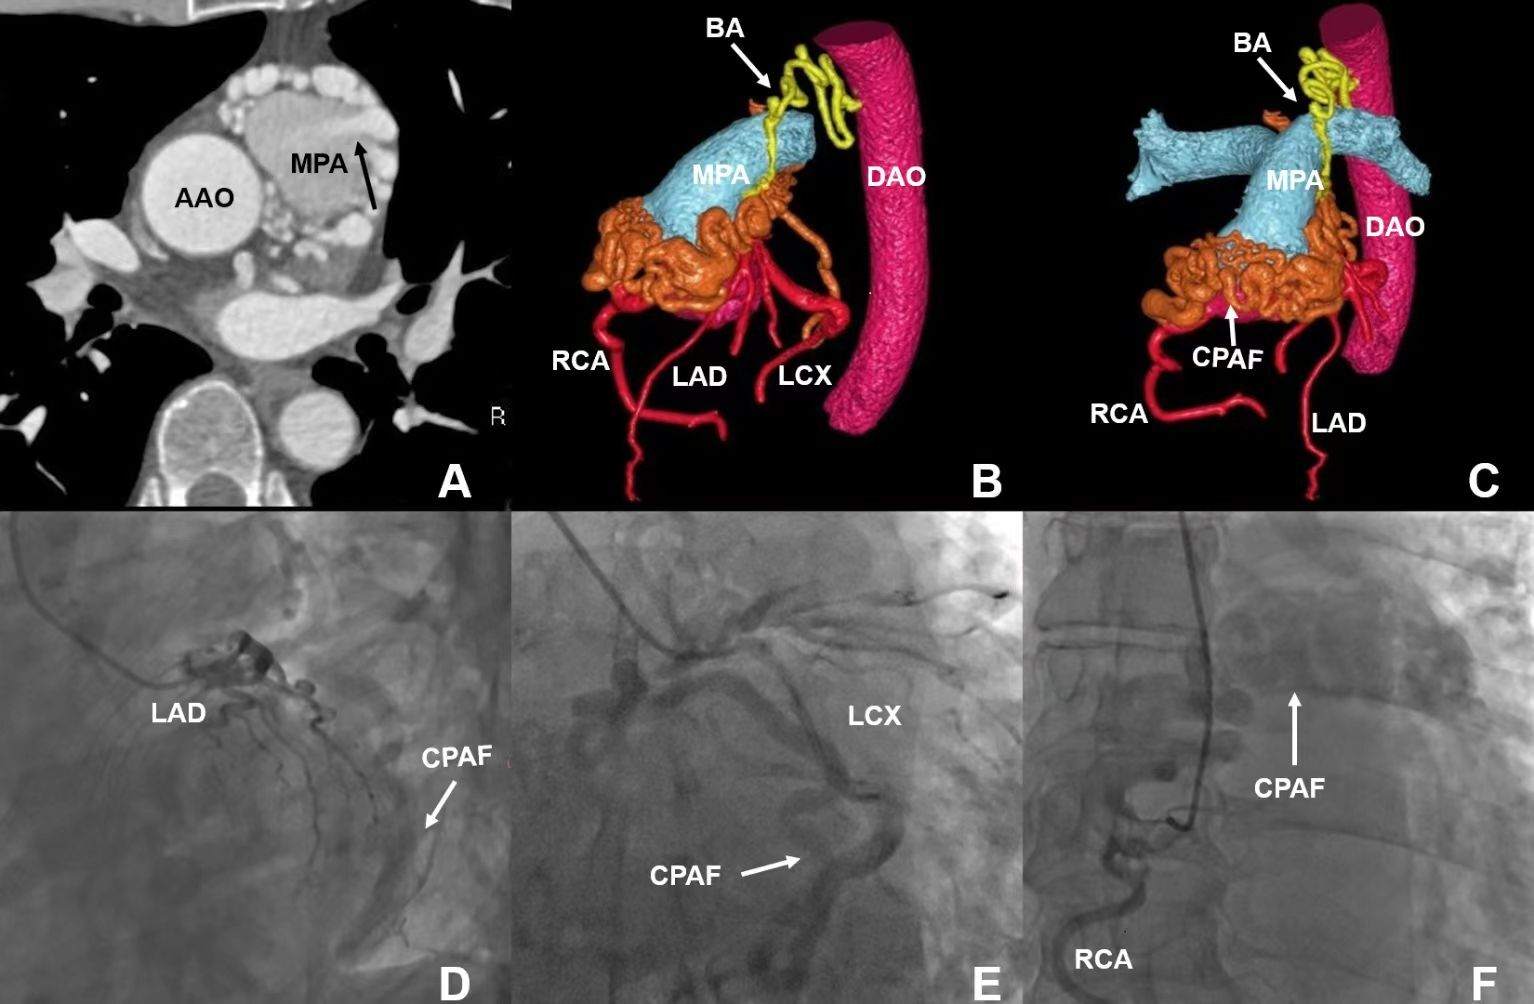

A 51-year-old man presented with palpitations and shortness of breath for the past 4 years. Findings from electrocardiography and laboratory tests performed after physical examination were unremarkable. Coronary computed tomography angiography (CCTA) was performed to rule out coronary heart disease.

The CCTA showed that several large and tortuous vessels originating from the left main coronary artery, left circumflex artery, and proximal right coronary artery were connected to the pulmonary artery, forming a coronary-pulmonary artery fistula (CPAF) with the formation of multiple aneurysms (Figure). A bronchial artery from the descending aorta was also involved in the CPAF. Coronary angiography confirmed the CCTA findings (Figure, Videos 1-3).

CPAF is rare, accounting for about 0.3% of all congenital heart conditions. It may originate from any branch of the coronary artery, and both left and right coronary arteries are involved in about 5% of cases.1,2 However, CPAF involving 3 coronary arteries and bronchial arteries with the formation of multiple aneurysms is much rarer. CCTA can clearly depict the morphology and position of the fistula, allowing surgeons to evaluate the anatomic delineation, origin, and outflow site of the fistula.